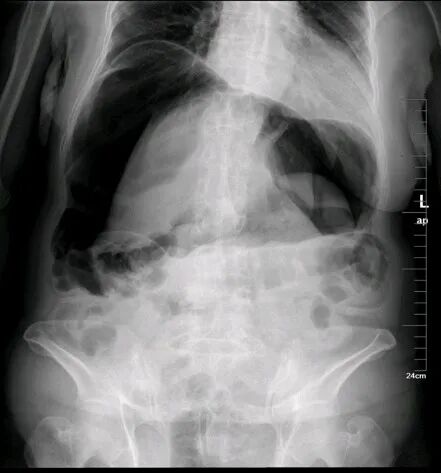

任何原因引起的肠内容物通过障碍统称肠梗阻。它是常见的外科急腹症之一。有时急性肠梗阻诊断困难,病情发展快,常致患者死亡。目前的死亡率一般为5%~10%,有绞窄性肠梗阻者为10%~20%。水、电解质与酸碱平衡失调,以及患者年龄大合并心肺功能不全等常为死亡原因。

弹簧征、液气平面、拱形肠管扩张